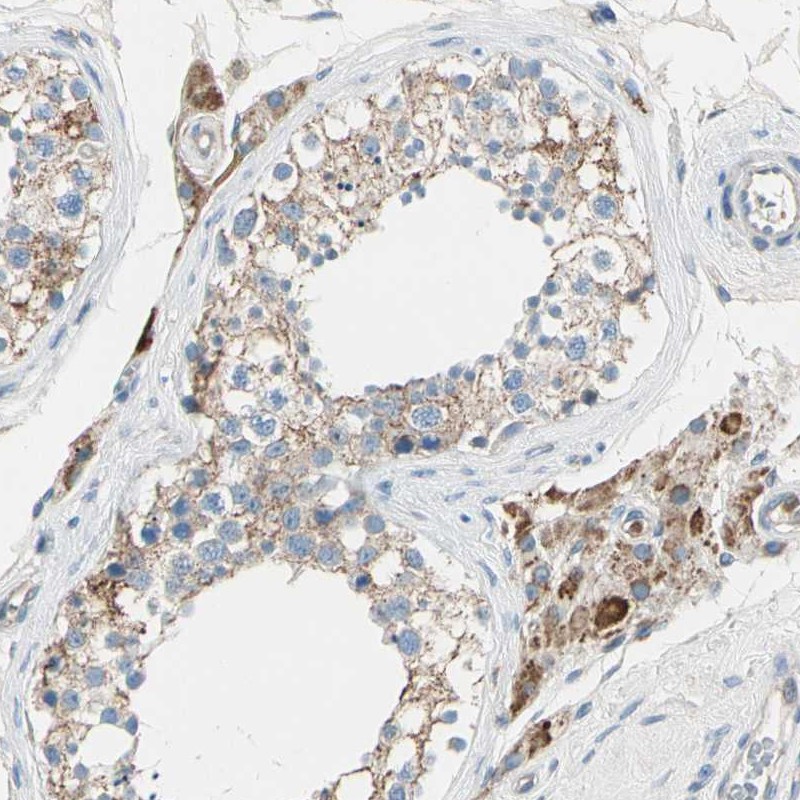

Immunohistochemical staining of human testis shows strong cytoplasmic positivity in cells in seminiferus ducts, leydig cells.